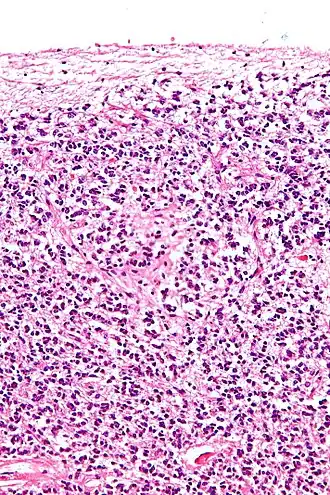

![]() Cross-section of pineal gland displaying pinealocytes and other cells | |

Pinealocytes are the main cells contained in the pineal gland, located behind the third ventricle and between the two hemispheres of the brain. The primary function of the pinealocytes is the secretion of the hormone melatonin, important in the regulation of circadian rhythms.[1] In humans, the suprachiasmatic nucleus of the hypothalamus communicates the message of darkness to the pinealocytes, and as a result, controls the day and night cycle.[2] It has been suggested that pinealocytes are derived from photoreceptor cells.[3][4] Research has also shown the decline in the number of pinealocytes by way of apoptosis as the age of the organism increases.[5] There are two different types of pinealocytes, type I and type II, which have been classified based on certain properties including shape, presence or absence of infolding of the nuclear envelope, and composition of the cytoplasm.